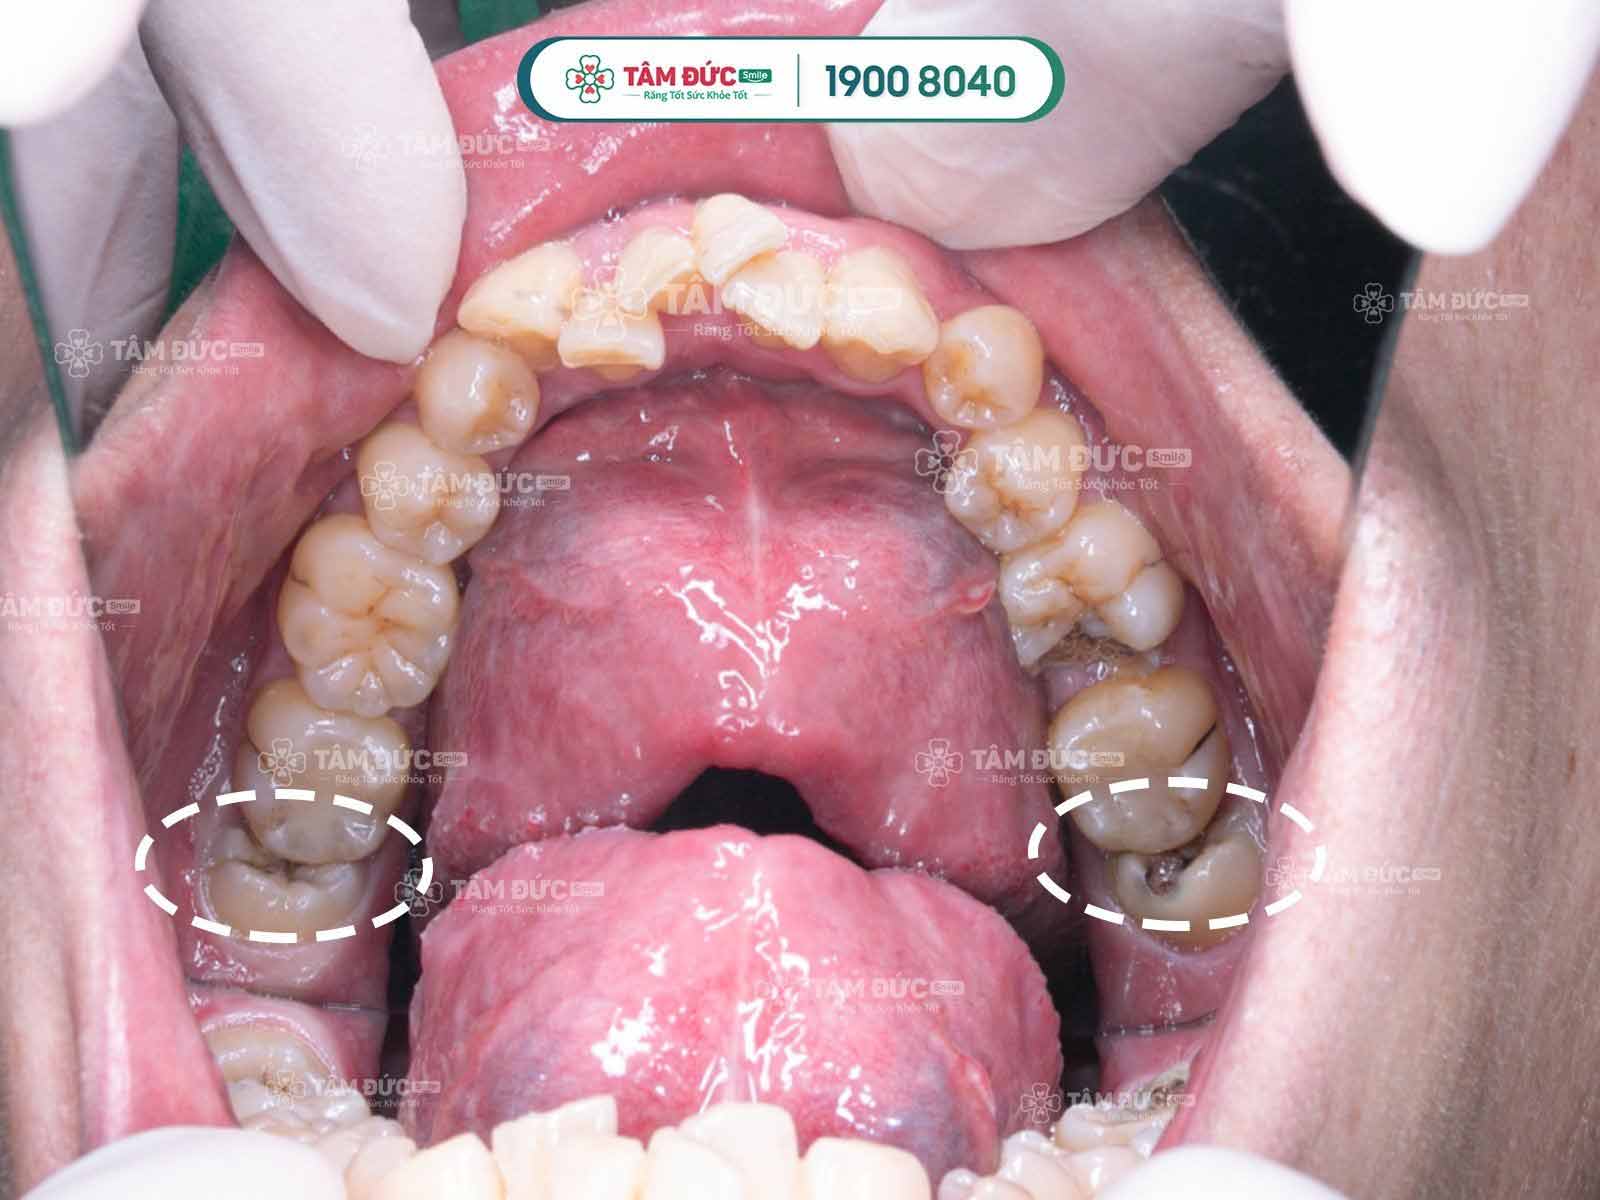

răng khôn mọc ngầm và có hình dạng kỳ dị

Cần phải nhổ răng khôn mọc lệch càng sớm càng tốt

Tác hại của việc răng khôn mọc lệch:

• Thức ăn sẽ nhồi nhét giữa răng khôn và răng kế bên nếu không vệ sinh được sẽ gây hôi miệng, sâu răng, nghiêm trọng sẽ gây viêm tủy răng số 7 kế bên.

• Răng khôn mọc đâm vào răng kế bên làm cho các răng cửa phía trước dồn lại, chen chúc lệch lạc mất thẩm mỹ và sai khớp cắn.

• Qua kết quả chụp phim thấy răng khôn mọc lệch, đâm vào răng số 7

• Nướu chỗ răng khôn thường bị nhiễm trùng sưng đau lặp đi lặp lại nhiều lần.

• Nhiễm trùng răng khôn kéo dài gây hoại tử xương, viêm mô tế bào, sưng mặt, một số ít trường hợp chuyển sang ung thư phải cắt xương hàm.